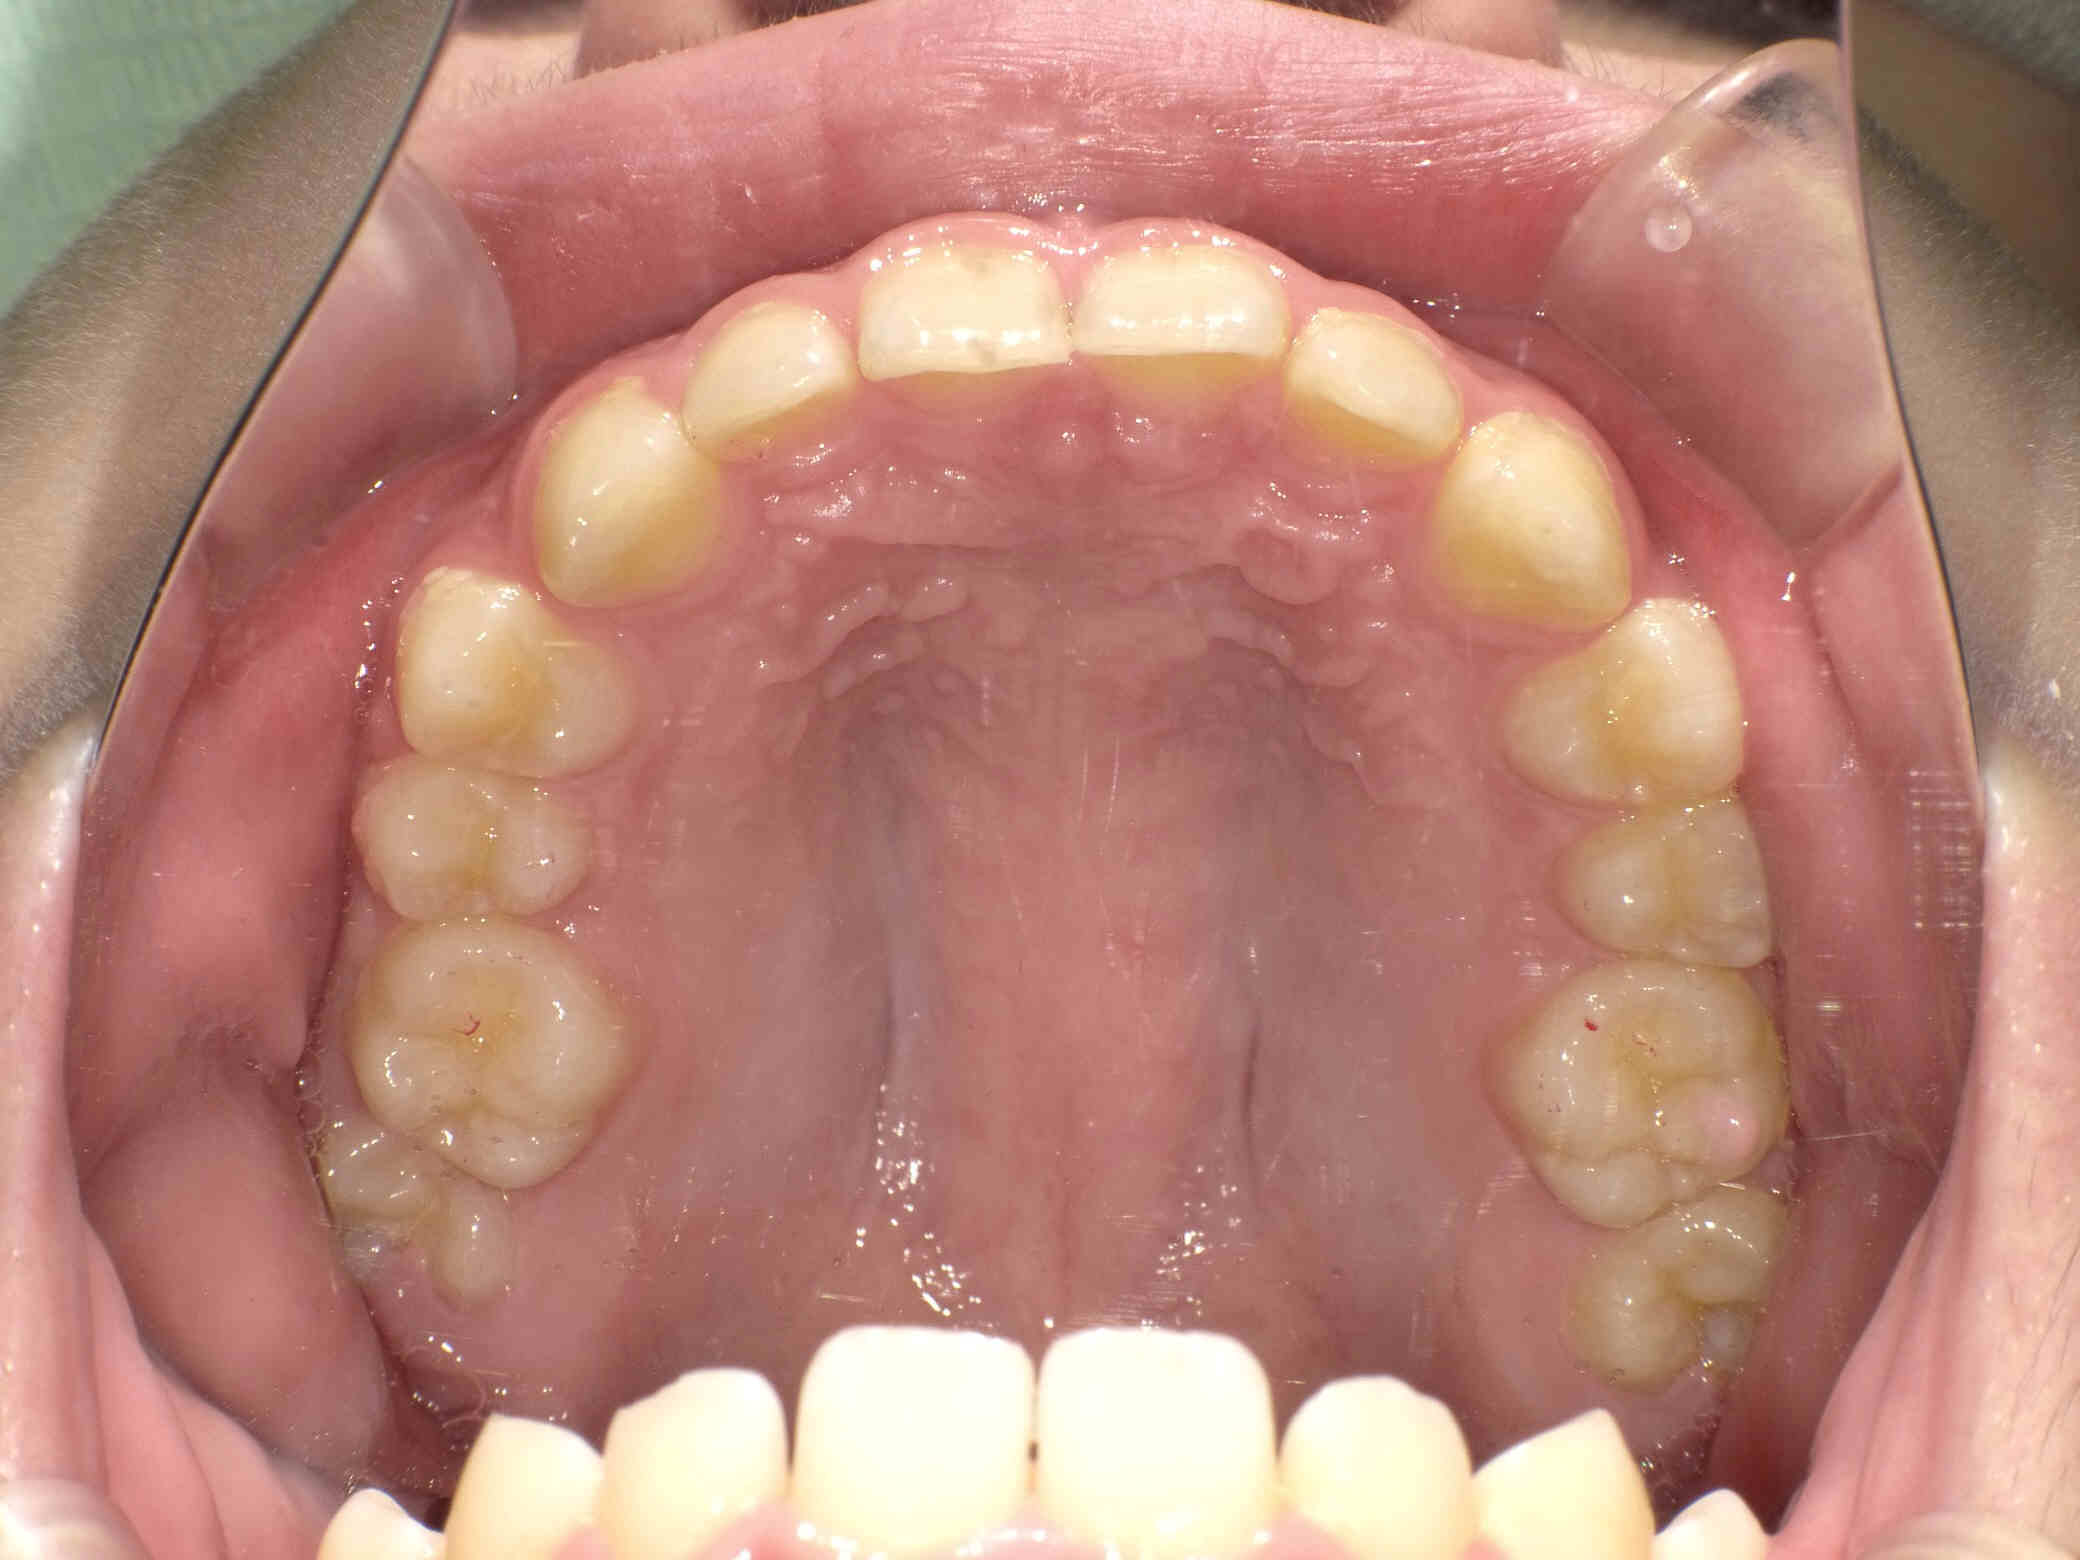

12歳6ヶ月〜スタートです。

やや出っ歯傾向で、噛み合わせが深く

歯並びがデコボコな鋏上咬合(はさみじょうこうごう)という状況でした。

上下の歯がすれ違っている状態で、一部の歯に過度の負担がかかってしまいます。

今回はご希望のワイヤー矯正で治療を行い、スタートから1年半で美しい歯並びに改善しました。